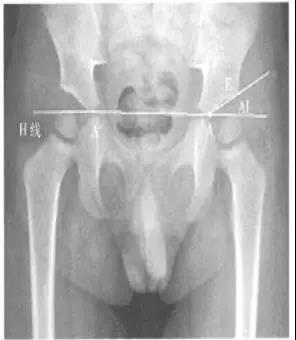

- 髋臼指数(actebular index,AI,亦称髋臼角):髂骨最下缘与髋臼最外缘的连线与H线的夹角(H线,即Hilgenreiner线,组成两侧髋臼髂骨最下缘的连线),适合于“Y”型软骨尚未闭合的儿童(≤10岁)髋臼的测量。

- 正常值:国外一些学者也测量了1~2岁婴幼儿的正常值范围,认为1岁婴儿的正常值在25°~30°之间,2岁一般低于20°,而超过30°为异常。

- 临床意义:评价髋臼发育和髋臼对股骨头的覆盖情况。